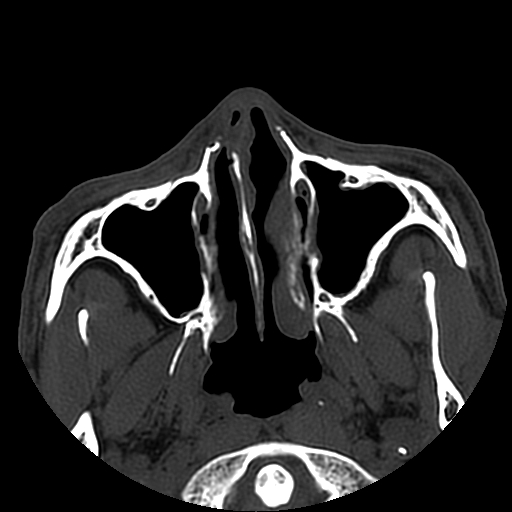

以下是引用liaoqiang在2008-7-16 21:15:00的发言:[br]右侧鼻骨骨折

以下是引用zxd95在2008-7-16 21:39:00的发言:[br]右侧上颌骨额突骨折。[br][br][br][br]